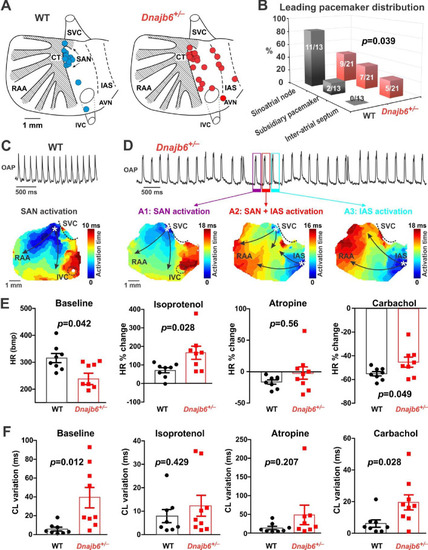

SAN dysfunction in the Dnajb6+/- mice. (A) Leading pacemakers were located and plotted from both WT (blue dots) and Dnajb6+/- (red dots) mice. One mouse could have multiple leading pacemaker locations due to the competing pacemakers and ectopic activities. SVC and IVC, superior and inferior vena cava; RAA, right atrial appendage; CT, crista terminalis; IAS, inter-atrial septum; AVN, atrioventricular node. Distribution of the leading pacemakers is summarized in panel. (B) Majority of leading pacemakers located within the SAN area in WT, whereas, in Dnajb6+/- mice, significant increase of leading pacemakers locating in subsidiary pacemaker area and IAS was observed. p-value by Fisher exact test. (C–D) Activation map based on the optical mapping of action potentials showed representative leading pacemaker locations in WT (SAN) and Dnajb6+/- mice (SAN and IAS areas). (E) Optical mapping on isolated atrial preparation showed bradycardia (baseline) and different responses of heart rate during isoproterenol, atropine, and carbachol stimulations between WT and Dnajb6+/- mice. N=7–9 mice per group. Unpaired student’s t-test. (F) Increased cycle length (CL) variation was observed in Dnajb6+/- isolated atrial preparations during different autonomic stimulations. N = 7–9 mice per group, unpaired student’s t-test. |